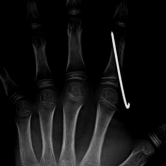

Röntgenbilder